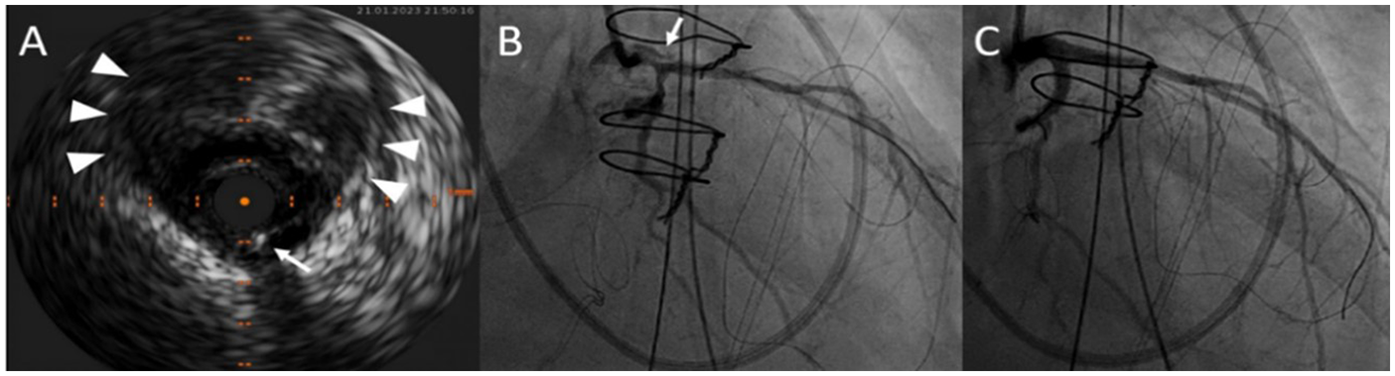

After gaining radial access, a 6 French Judkins left 4.0 guide was advanced to the left main ostium. To prevent the dissection progression, both ostia left anterior descending artery (LAD) and the left circumflex artery (LCX) had to be secured with a stent. The guidewire was advanced in the mentioned arteries without any contrast injection. Correct position of the wires in the true lumen was confirmed by intravascular ultrasound (Figure 5). After wiring the LAD and the LCX, the first contrast injection confirmed the dissection with contrast dye spreading in the false lumen and retrograde towards the aortic root. With no further delay, LAD, and LCX were stented using a nano-crush technique to the edge of the LM ostium without protrusion into the aorta. A Boston Scientific Synergy Megatron 3.5/20 mm stent was used for the LAD, and a Boston Scientific Synergy 3.0/16 mm for the LCX with excellent results. To better assess the result, we performed the IVUS again after stent deployment. The patient was given an antiplatelet therapy with 500 mg Aspirin IV at the start of the procedure and a loading dose of 600 mg Clopidogrel after the PCI. After the intervention, an improvement of the ejection fraction to 40% and a reduction of the residual mitral regurgitation from severe to mild was noticed. The patient was extubated on the fourth postoperative day without neurological impairment. She was transferred to the rehabilitation center on the sixth postoperative day (Figure 2) and returned home on the 42nd postoperative day after she made a full recovery. The patient was maintained on dual antiplatelet therapy consisting of Aspirin and Clopidogrel for 12 months.

Figure 5

After wiring both the left anterior descending artery and the left circumflex artery, intravascular ultrasound of the left main coronary artery confirmed the correct wire position (white arrows) in the true lumen. The white arrowheads point at the large false lumen (A). RAO projection in the coronary angiogram displaying dissection narrowing of the left main ostium and white arrow points at the false lumen (B). Postoperative result after LAD and LCX stenting with a nano-crush technique (C).